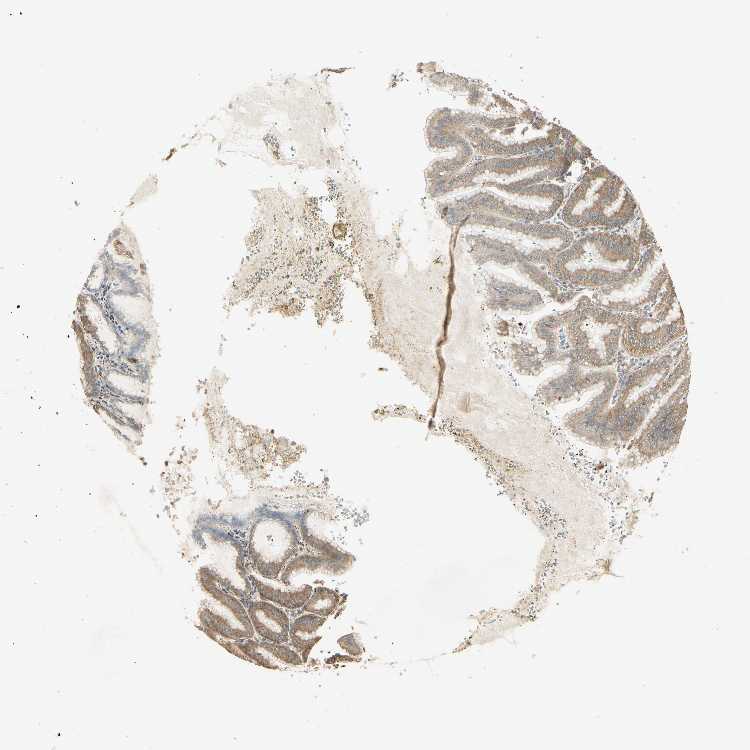

STOMACH 1 - Antibody stainingi

Antibody staining in the annotated cell types in the current human tissue is reported as not detected, low, medium, or high, based on conventional immunohistochemistry profiling in selected tissues. This score is based on the combination of the staining intensity and fraction of stained cells.

Each image is clickable and will lead to virtual microscopy that enables deeper exploration of all samples and also displays staining intensity scores, fraction scores and subcellular localization as well as patient and tissue information for each sample.

Antibody HPA008425

Glandular cells High

STOMACH 2 - Antibody stainingi

Glandular cells Medium